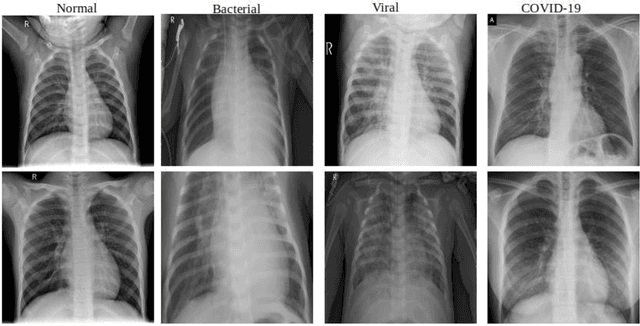

Abstract:In the last few months, the novel COVID19 pandemic has spread all over the world. Due to its easy transmission, developing techniques to accurately and easily identify the presence of COVID19 and distinguish it from other forms of flu and pneumonia is crucial. Recent research has shown that the chest Xrays of patients suffering from COVID19 depicts certain abnormalities in the radiography. However, those approaches are closed source and not made available to the research community for re-producibility and gaining deeper insight. The goal of this work is to build open source and open access datasets and present an accurate Convolutional Neural Network framework for differentiating COVID19 cases from other pneumonia cases. Our work utilizes state of the art training techniques including progressive resizing, cyclical learning rate finding and discriminative learning rates to training fast and accurate residual neural networks. Using these techniques, we showed the state of the art results on the open-access COVID-19 dataset. This work presents a 3-step technique to fine-tune a pre-trained ResNet-50 architecture to improve model performance and reduce training time. We call it COVIDResNet. This is achieved through progressively re-sizing of input images to 128x128x3, 224x224x3, and 229x229x3 pixels and fine-tuning the network at each stage. This approach along with the automatic learning rate selection enabled us to achieve the state of the art accuracy of 96.23% (on all the classes) on the COVIDx dataset with only 41 epochs. This work presented a computationally efficient and highly accurate model for multi-class classification of three different infection types from along with Normal individuals. This model can help in the early screening of COVID19 cases and help reduce the burden on healthcare systems.